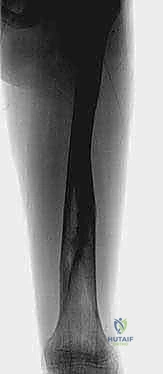

التثبيت الخارجي هو تقنية جراحية يتم فيها إدخال دبابيس أو براغي معدنية خاصة من خلال الجلد إلى العظم السليم أعلى وأسفل منطقة الكسر. يتم بعد ذلك توصيل هذه الدبابيس بإطار معدني أو كربوني صلب خارج الجسم.

- الحفاظ على الأنسجة الرخوة: لا يتطلب شقاً جراحياً كبيراً لفتح العظم، مما يحافظ على التروية الدموية الطبيعية للعظم (Hematoma) والتي تحتوي على الخلايا الجذعية اللازمة للشفاء السريع.

- التعامل مع الكسور المفتوحة: إذا كان العظم قد اخترق الجلد، فإن التثبيت الداخلي قد يسبب تلوثاً عميقاً. التثبيت الخارجي يبعد المعدات عن الجرح الملوث ويسمح بتنظيفه يومياً.

- تعديل المحاذاة بعد الجراحة: يتيح الجهاز الخارجي للطبيب إجراء تعديلات دقيقة على طول واستقامة العظم حتى بعد انتهاء العملية وأثناء فترة الشفاء.

- حماية مراكز النمو: يتم وضع الدبابيس ببراعة بعيداً عن صفائح النمو الحساسة.